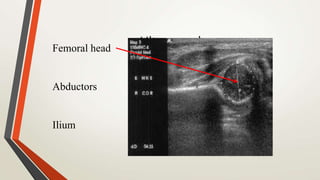

UltrasoundFemoral head

Abductors

Ilium